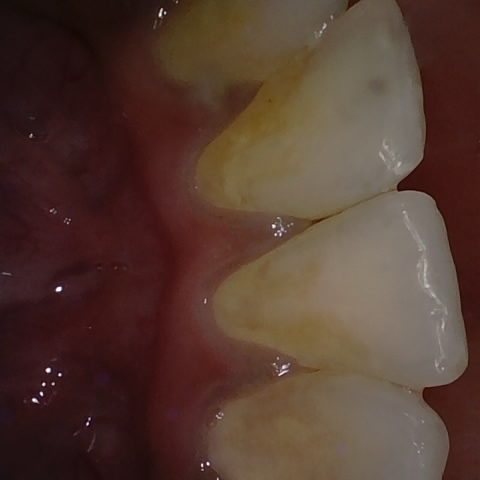

Annotated as "Good"